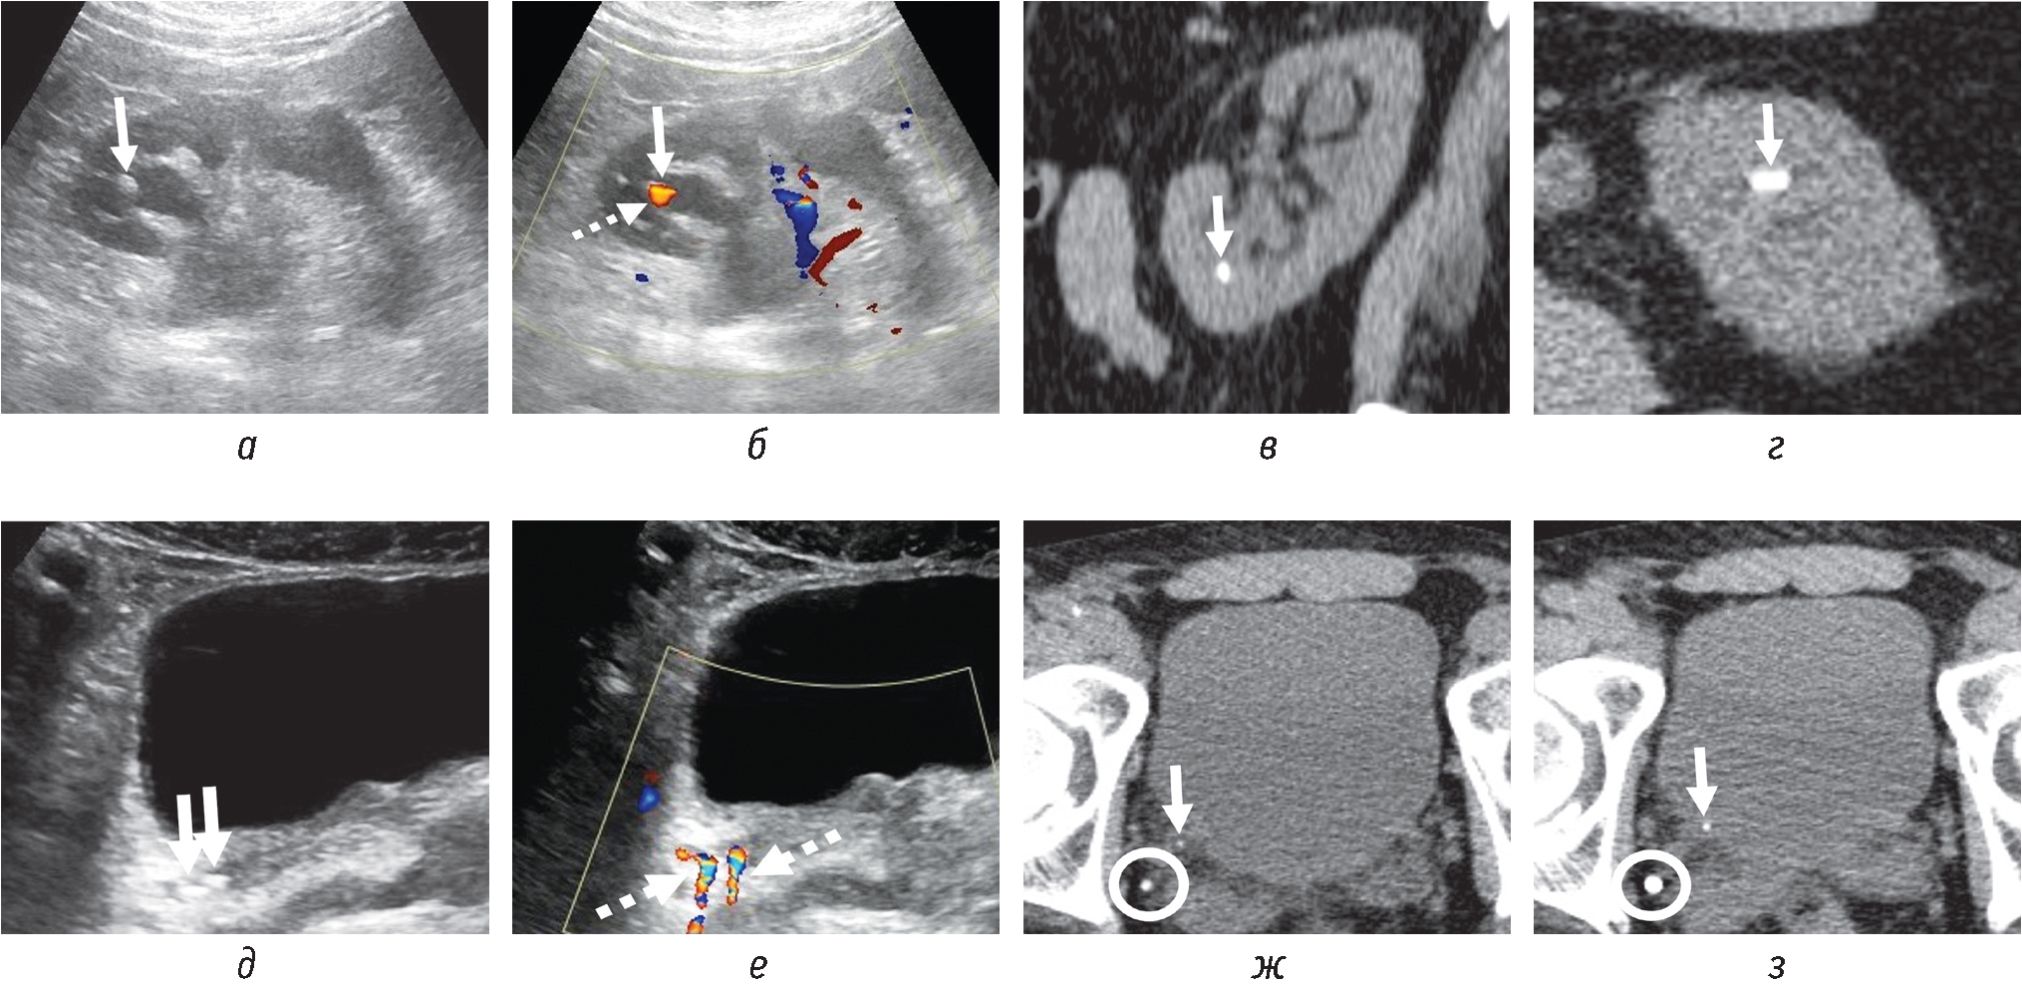

В последние годы внимание врачей УЗД обратил на себя так называемый артефакт мерцания (АМ), или артефакт «цветного хвоста кометы», возникающий в режиме цветового допплеровского картирования позади конкремента в МВП (рис. 1). АМ представляет собой комплексный феномен в виде фокуса/очага быстрой смены (мерцания) красного и синего цветов позади отражающего объекта, т. е. конкремента [5, 7].

Рис. 1. Трансабдоминальные сонограммы (а, в): два конкремента (сплошные стрелки) размерами 3 и 4 мм в нерасширенных чашечках без четкой акустической тени. АМ каждого из конкрементов указан пунктирными стрелками на соответствующих изображениях в режиме ЦДК справа (б, г)